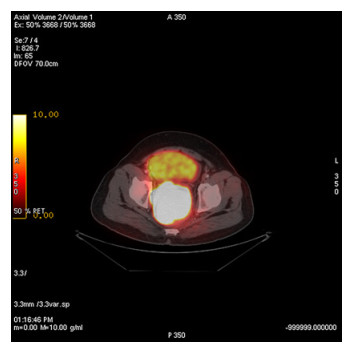

Abstract: Rectal malignancy is usually symptomatic due to its location, and most of the time presents with pain and bleeding due to its growth and ulceration. It is difficult to identify the primary as carcinoma or lymphoma based on symptoms only, as both have a similar presentation. As it presents the rarest form of histology, non-Hodgkin's lymphoma in the rectum is still difficult to diagnose initially, and its treatment is debatable. We describe the case of a 49-year-old male from Bangladesh with the same presentation. His treatment was delayed for more than a month as immunohistochemistry and staging delayed the final diagnosis. The disease was diagnosed as stage IE with the help of a positron emission tomography (PET)-CT scan, and due to the local progression the patient had a massive rectal bleeding that needed an urgent intervention. Radiotherapy was applied to stop the bleeding. Hypofraction followed by a conventional fraction of external beam radiotherapy (EBRT) with a total of 40 Gy was applied. Post-EBRT digital rectal examination showed no residual except scaring, and a PET scan was also negative for residual disease. Due to uncertainties and lack of any precious guideline, 6 cycles of adjuvant chemotherapy with the R-CHOP schedule were also completed. Without surgery, the combination of EBRT and chemotherapy helped to preserve the organ, and the patient has been disease free for more than 2.5 years since his treatment.